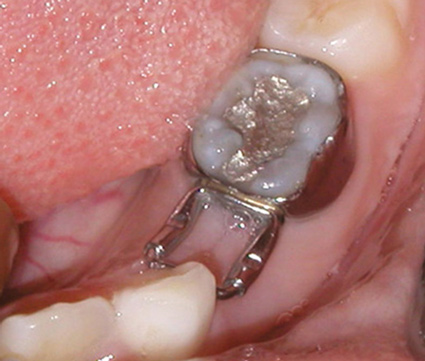

In cases of premature loss of primary teeth or missing permanent teeth, space maintenance is crucial.42 Possible causes of such tooth loss include caries, trauma, or a congenital disorder. If proper spacing is not maintained, mesial tooth drift may occur,43,44 which can lead to impaction or ectopic eruption of permanent teeth, as previously discussed. Various designs of space maintainers are available, depending on the location in the mouth that needs space preservation. Common devices include the Nance arch for the maxilla (Figure 15), a lower lingual holding arch for the mandible (Figure 16), and a band and loop or distal shoe for unilateral cases of space loss (Figure 17). Band and loop appliances seem to have the highest longevity intraorally; generally, unilateral devices fare better than their bilateral counterparts.45

Fig 17. Band and loop/distal shoe (unilateral).

Figure 17